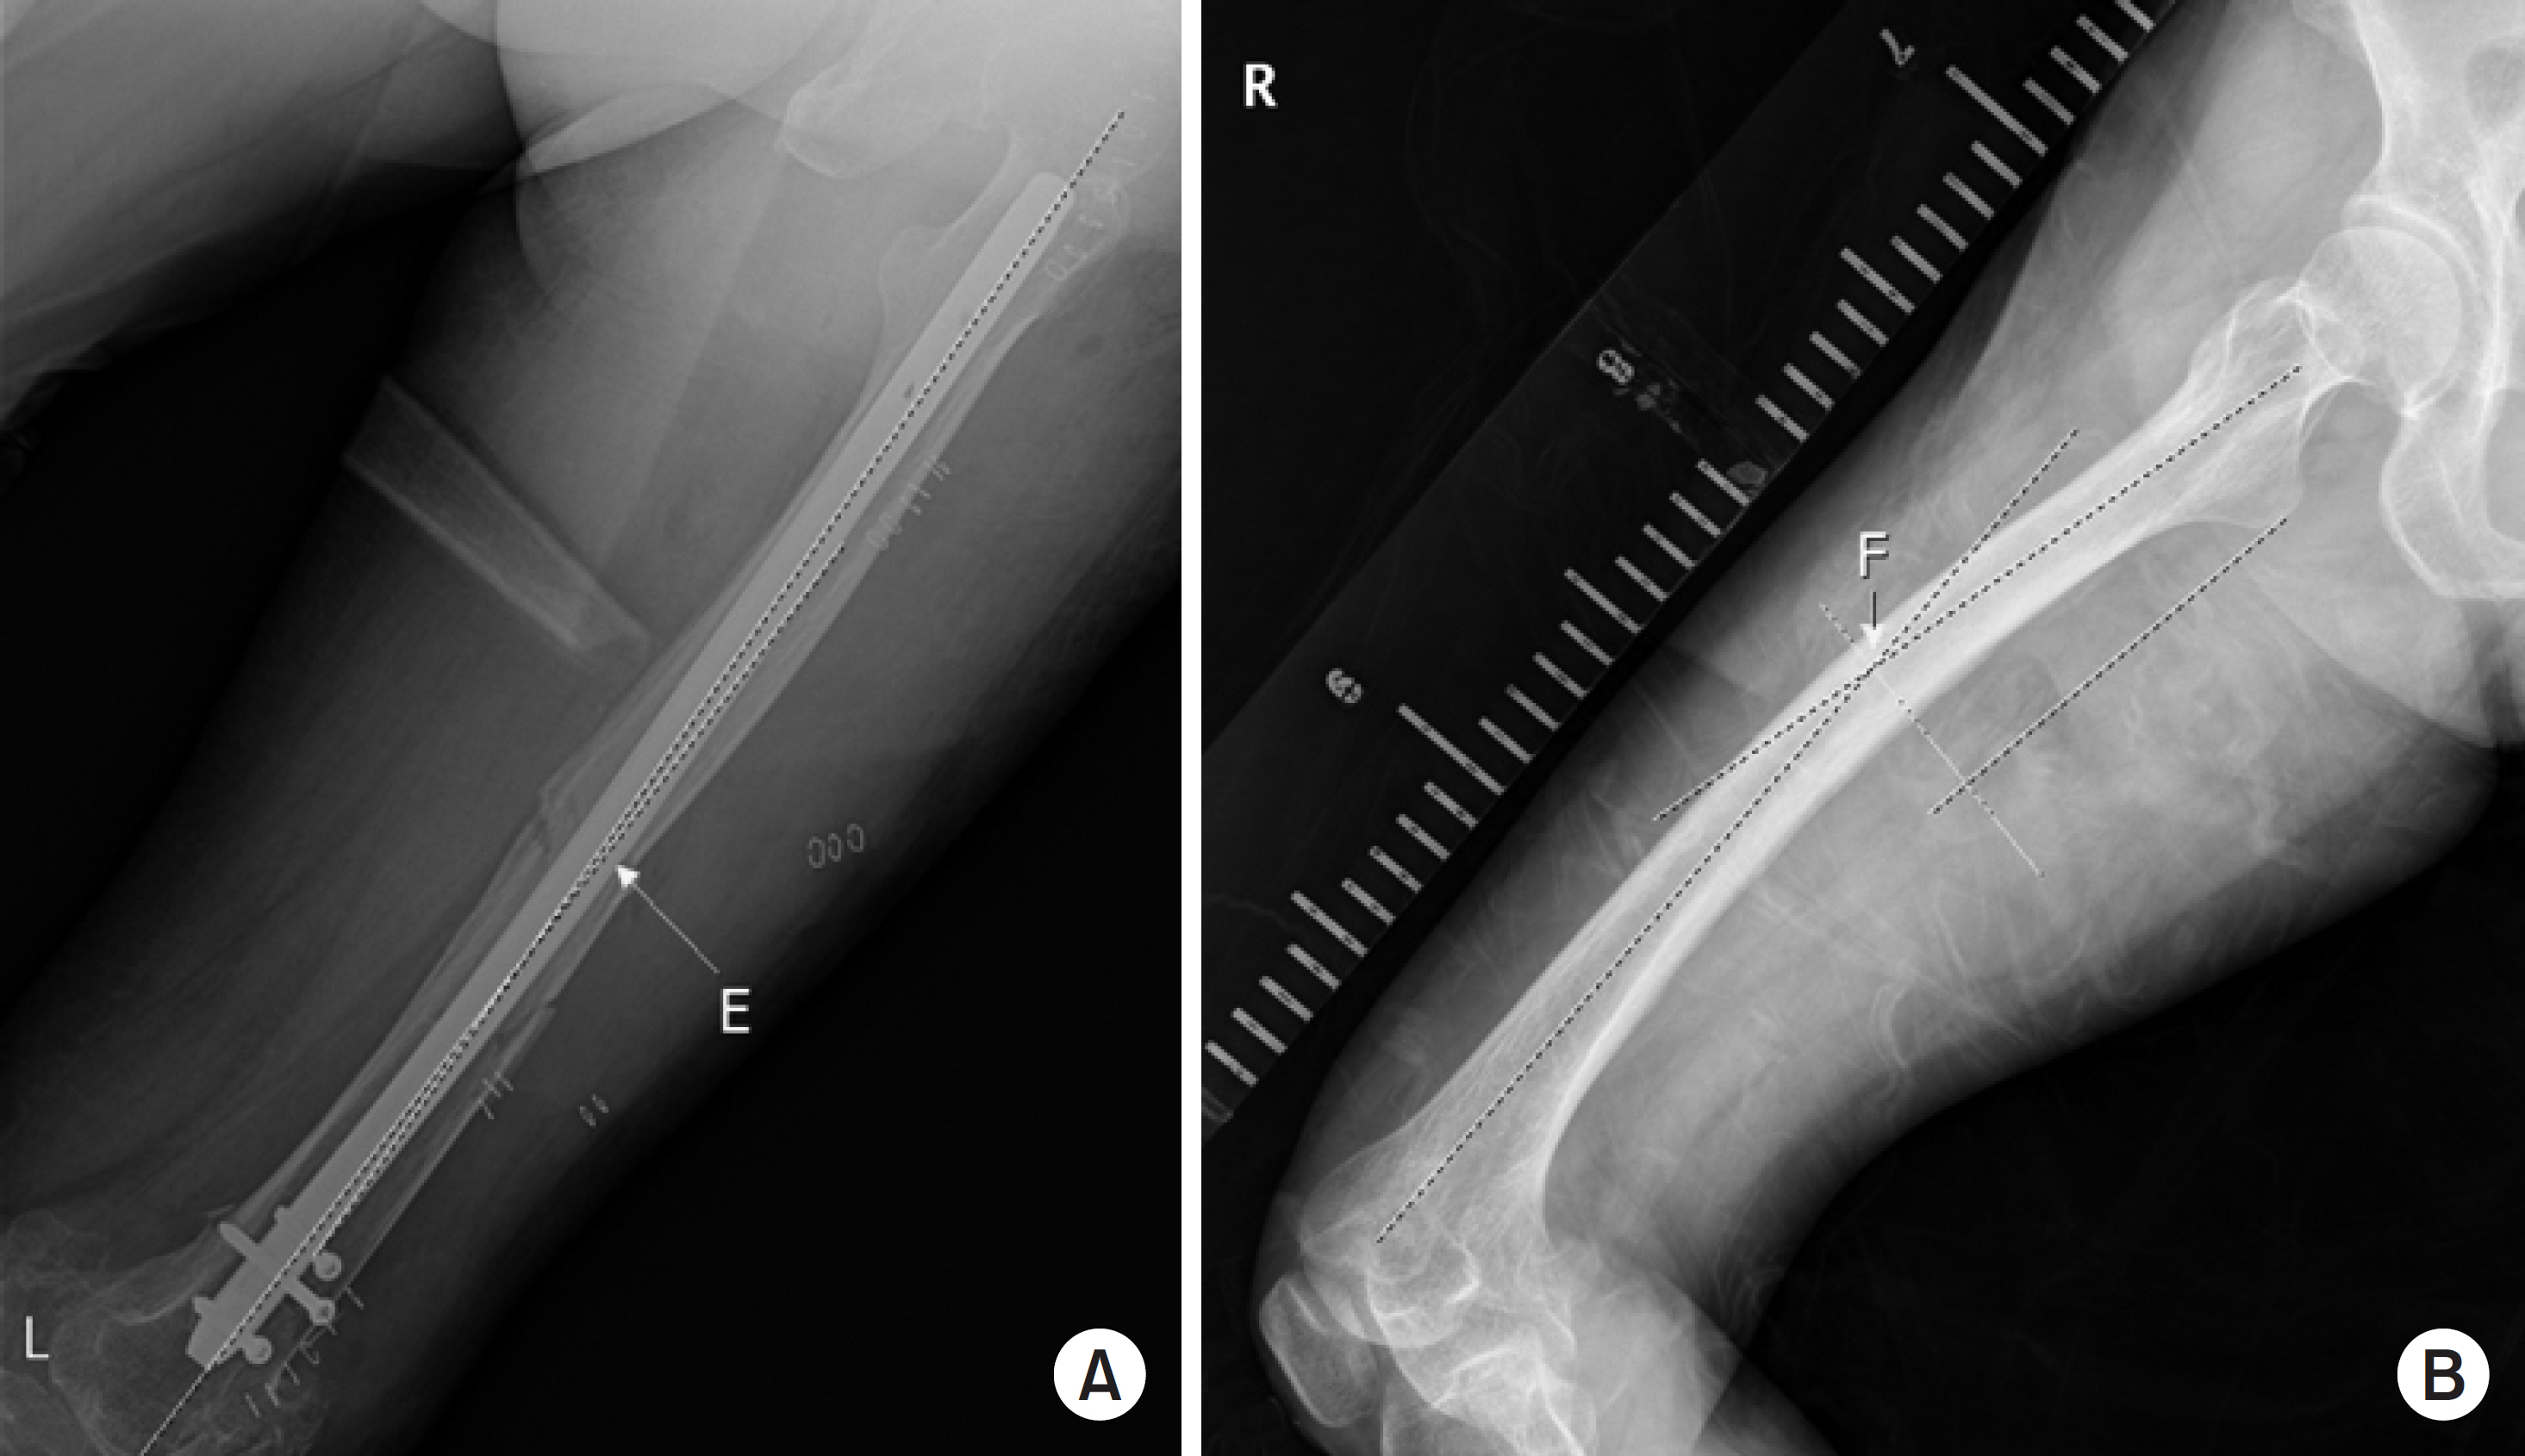

Fig. 3.

(A) The angle that the proximal and distal fragments make based on the fracture site in the coronal plane (letter ‘E’). (B) The value of the unaffected site on the basis of the affected site (letter ‘F’). If E-F is 0: neutral, (+): flexion, (–): extension.